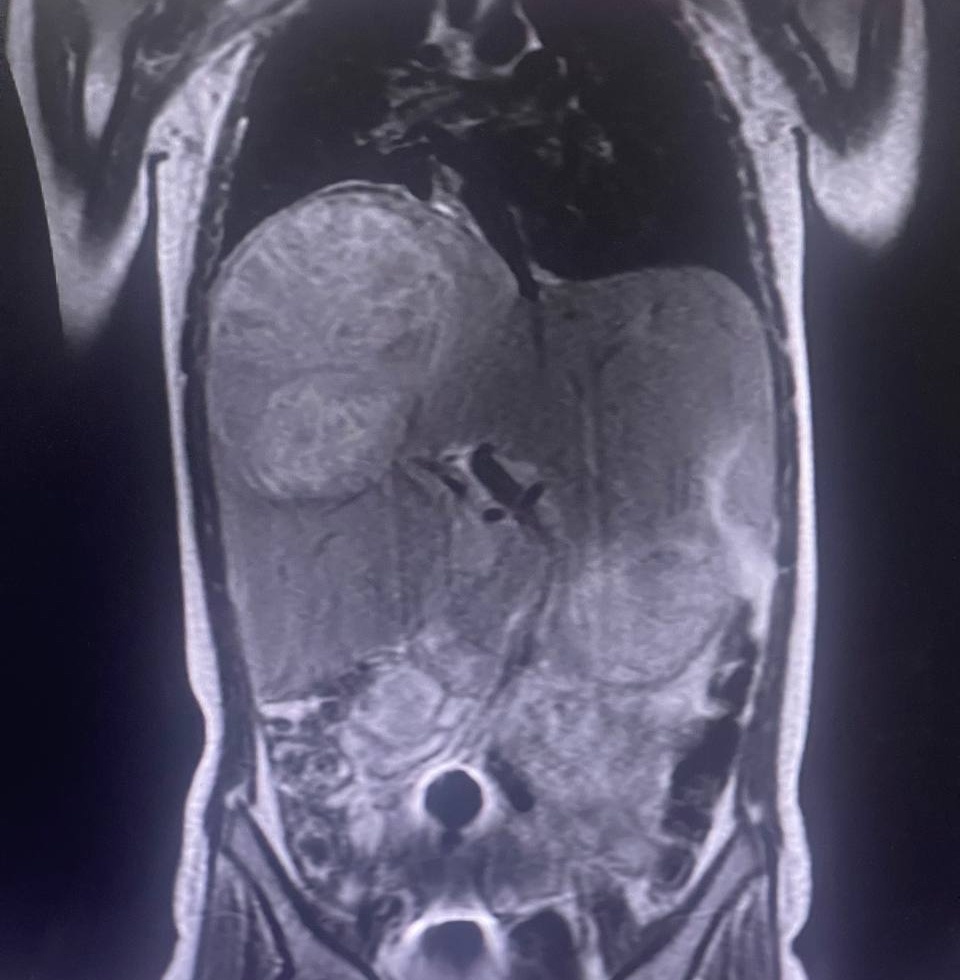

После прибытия в ЧОДКБ и проведения дополнительного обследования, наши специалисты диагностировали огромный многокамерный абсцесс правой доли печени, поразивший 3 из 4 сегментов. Размер абсцесса составлял 10-12 см. На снимках было видно, что из-за этого уже страдали другие органы – увеличенная печень их сдавливала.

Врачи приняли решение о проведении сложной операции – удалении правой доли печени, не вскрывая абсцесс. Это был единственный способ помочь ребенку, так как абсцесс был многокамерным и пункция была бы неэффективна. Предположительно, причиной абсцесса стала нагноившаяся паразитарная киста.